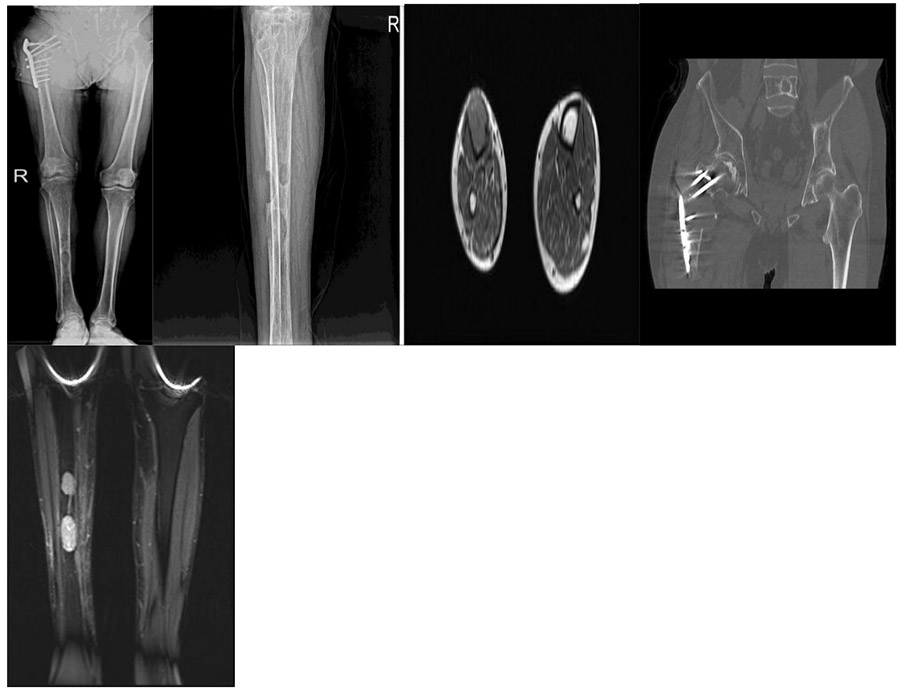

CASE 52: A patient underwent surgery due to the risk of fracture caused by metastasis of thyroid cancer to the right tibia.

Before the surgery: X-ray shows material failure in the right proximal femur, CT scan shows recurrence in the right proximal femur, and MRI shows metastatic foci in two locations in the right tibia.